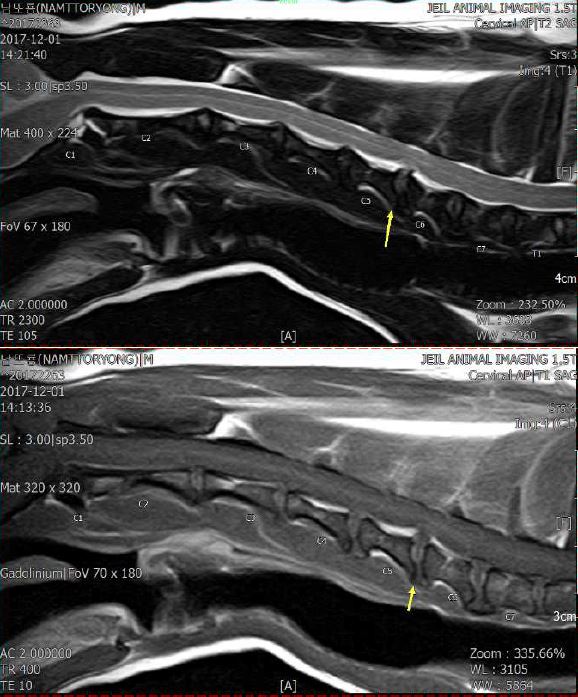

동물병원에 가서 영상보여줬어요 정확한 이유를 알기 위해서는 MRI를 찍어봐야해요 마취가 필요해서 대형견은 권하지않습니다 설사가 있어도 노출되요 할 수 없다고 말하는 이유입니다. ㅠㅠ 신경계의 이상으로 근육이 신경을 압박하여 머리를 흔드는 것일수도 있습니다 노령견의 대부분은 사지마비나 경련 등의 증상을 보입니다. 이상한 두려움 때문에 짖거나 울부 짖는다.잠 자기도 모르게 머리가 떨려서 나에게 다가와 조용히 나를 바라 보았다. ..부드럽고 늠름한 우리 전백이 ㅠㅠㅠㅠㅠ